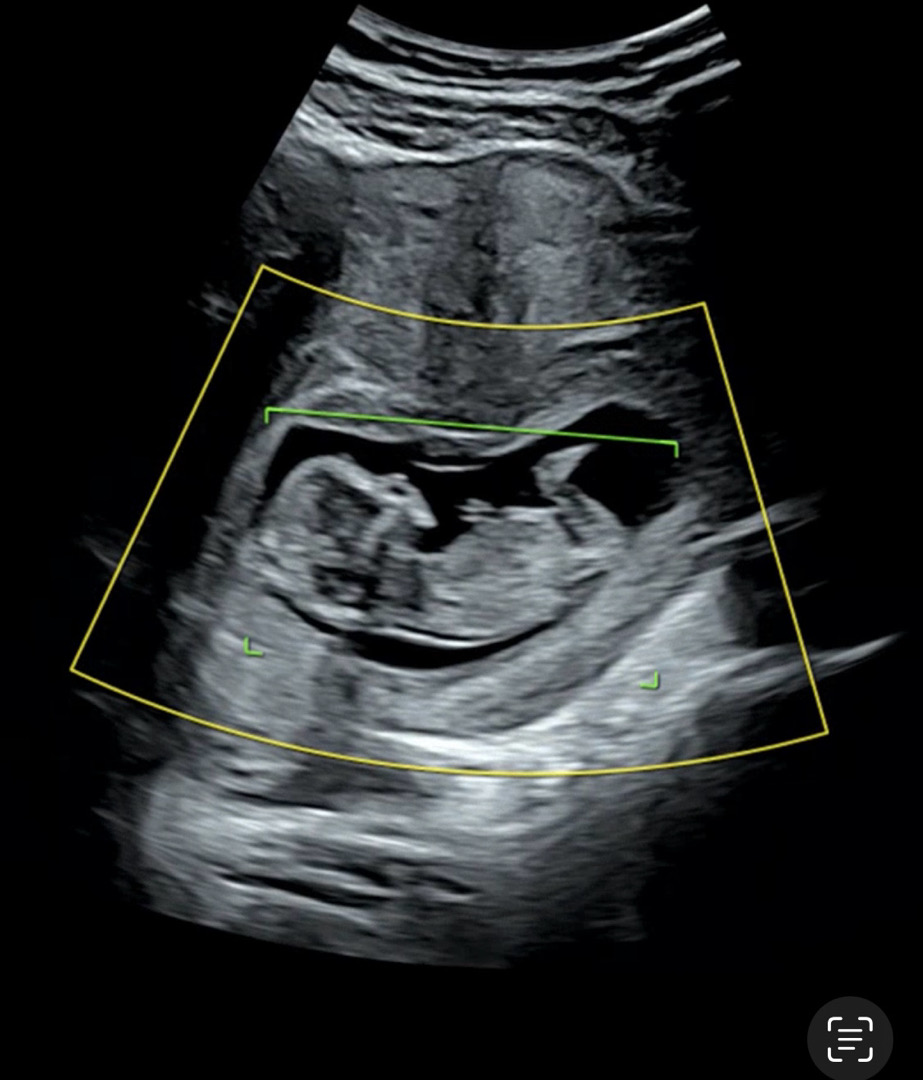

오늘 12주 초음파인데 각도법 보이나요?

예전엔 16주까지 기다려야지~~ 했는데 사람마음이 너무 궁금하네요!